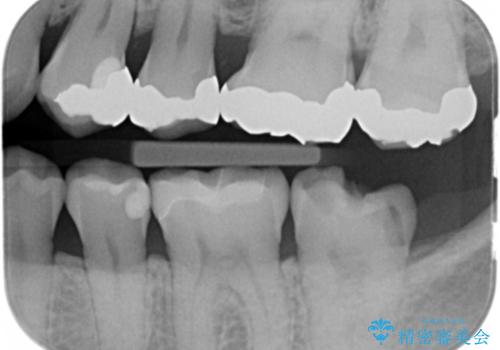

- 銀の詰め物が取れたとのことで来院。

詰め物の下には虫歯がありました。

白い物で治療して欲しいとのことで、セラミックの詰め物だと詰め物の範囲が大きく、割れてしまう可能性があるので

ジルコニアクラウン(被せもの)で治療を行いました。

銀の詰め物はかなり昔に治療されたそうです。

銀の詰め物は虫歯の再発リスクが高く、歯に痛みが出てしまうと歯の神経の治療もしないとならなくなってしまいます。